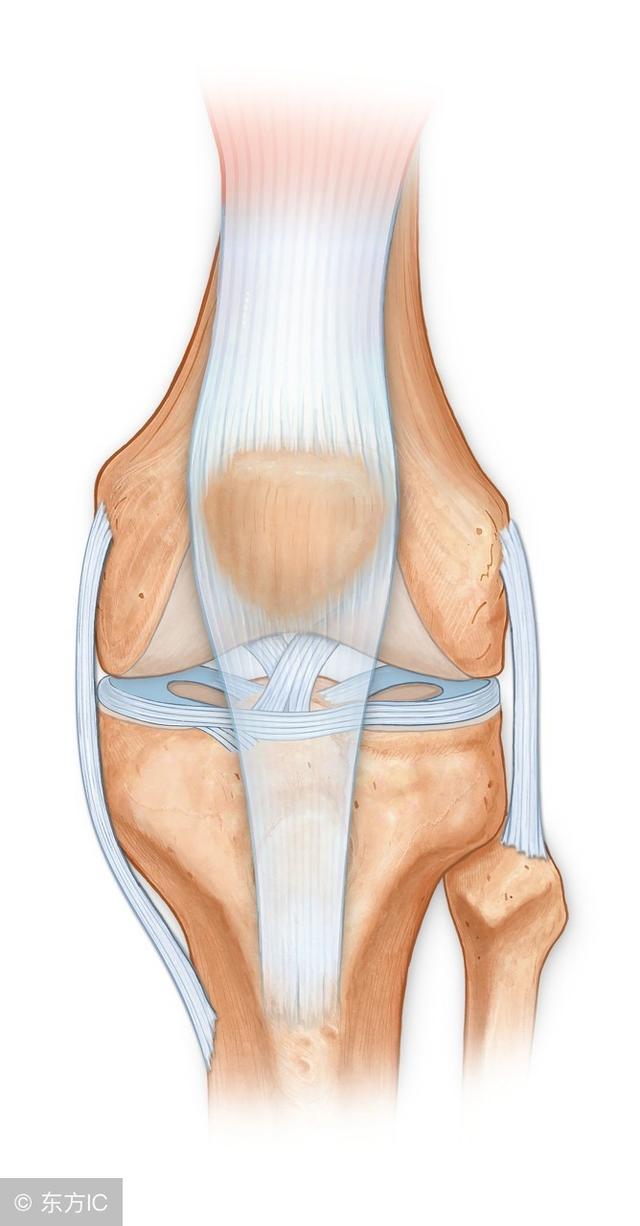

14、半月板损伤

发生于膝关节突然旋转损伤,如跑步者突然改变方向,也可发生于慢性退变过程中,尤其是有膝关节不稳定时,反复膝关节疼痛,交锁时加重,下蹲或膝关节旋转时可引发交锁,轻度积液,关节线压痛,股内侧肌萎缩, McMurray试验阳性 (阴性不能排除诊断)X线平片阴性。